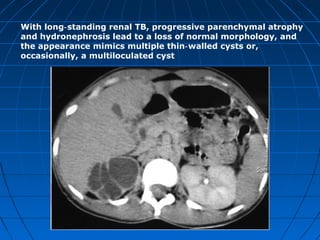

With long standing renal TB, progressive parenchymal atrophy‑

and hydronephrosis lead to a loss of normal morphology, and

the appearance mimics multiple thin walled cysts or,‑

occasionally, a multiloculated cyst